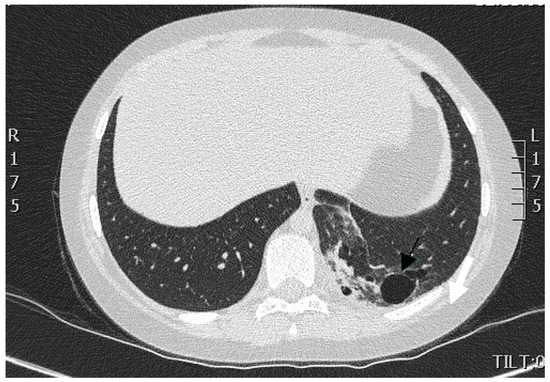

We performed multi-slice, contrast-enhanced CT scanning of the thorax and upper abdomen with subsequent multiplanar reconstruction. The lung tissue exhibited massive infiltration with cavities measuring 3 mm to 28 mm at the posterior-basal segment S10 of the left lower lobe (Figure 1).

Figure 1.

CT scan of the thorax. A portion of lung tissue contained cavities (indicated by arrow) and hyperdense scar formation located in the dorsomedial part of the lower lobe of the left lung.

There was no communication of the affected lung parenchyma with bronchi of the left inferior lobe. We noted no further infiltrative changes in the remainder of the left and right lungs. Contrast-enhanced CT scanning with 3D reconstruction showed normal configuration of the thoraco-abdominal aorta, celiac trunk, and renal arteries. The celiac trunk originated from the abdominal aorta at the level of the intervertebral space Th12-L1. The systemic feeding artery (proximal diameter of 5 mm) originated from the celiac trunk. This artery supplied the pulmonary intralobar sequestration in the inferior lobe of the left lung (Figure 2a,b).

Figure 2.

(a) Contrast-enhanced CT scan of the thoraco-abdominal aorta with 3D reconstruction of aorta, celiac trunk, and renal arteries. Note the feeding artery (indicated by arrow) with a diameter of 5 mm supplying the sequestration in the inferior lobe of the left lung (antero-posterior [AP] view). (b) Anomalous artery arising from the celiac trunk (artery indicated by arrow; lateral view).

When comparing the chest CT images obtained by the regional hospital with our contrast-enhanced CT image, we noted a partial regression of dystelectatic areas within the left inferior lobe of the lung, reduced fluid within the cyst-like lesions, and reduced pleural effusion. Thus, we established the diagnosis of intrapulmonary sequestration of the inferior lobe of the left lung complicated by infection and pleural effusion.